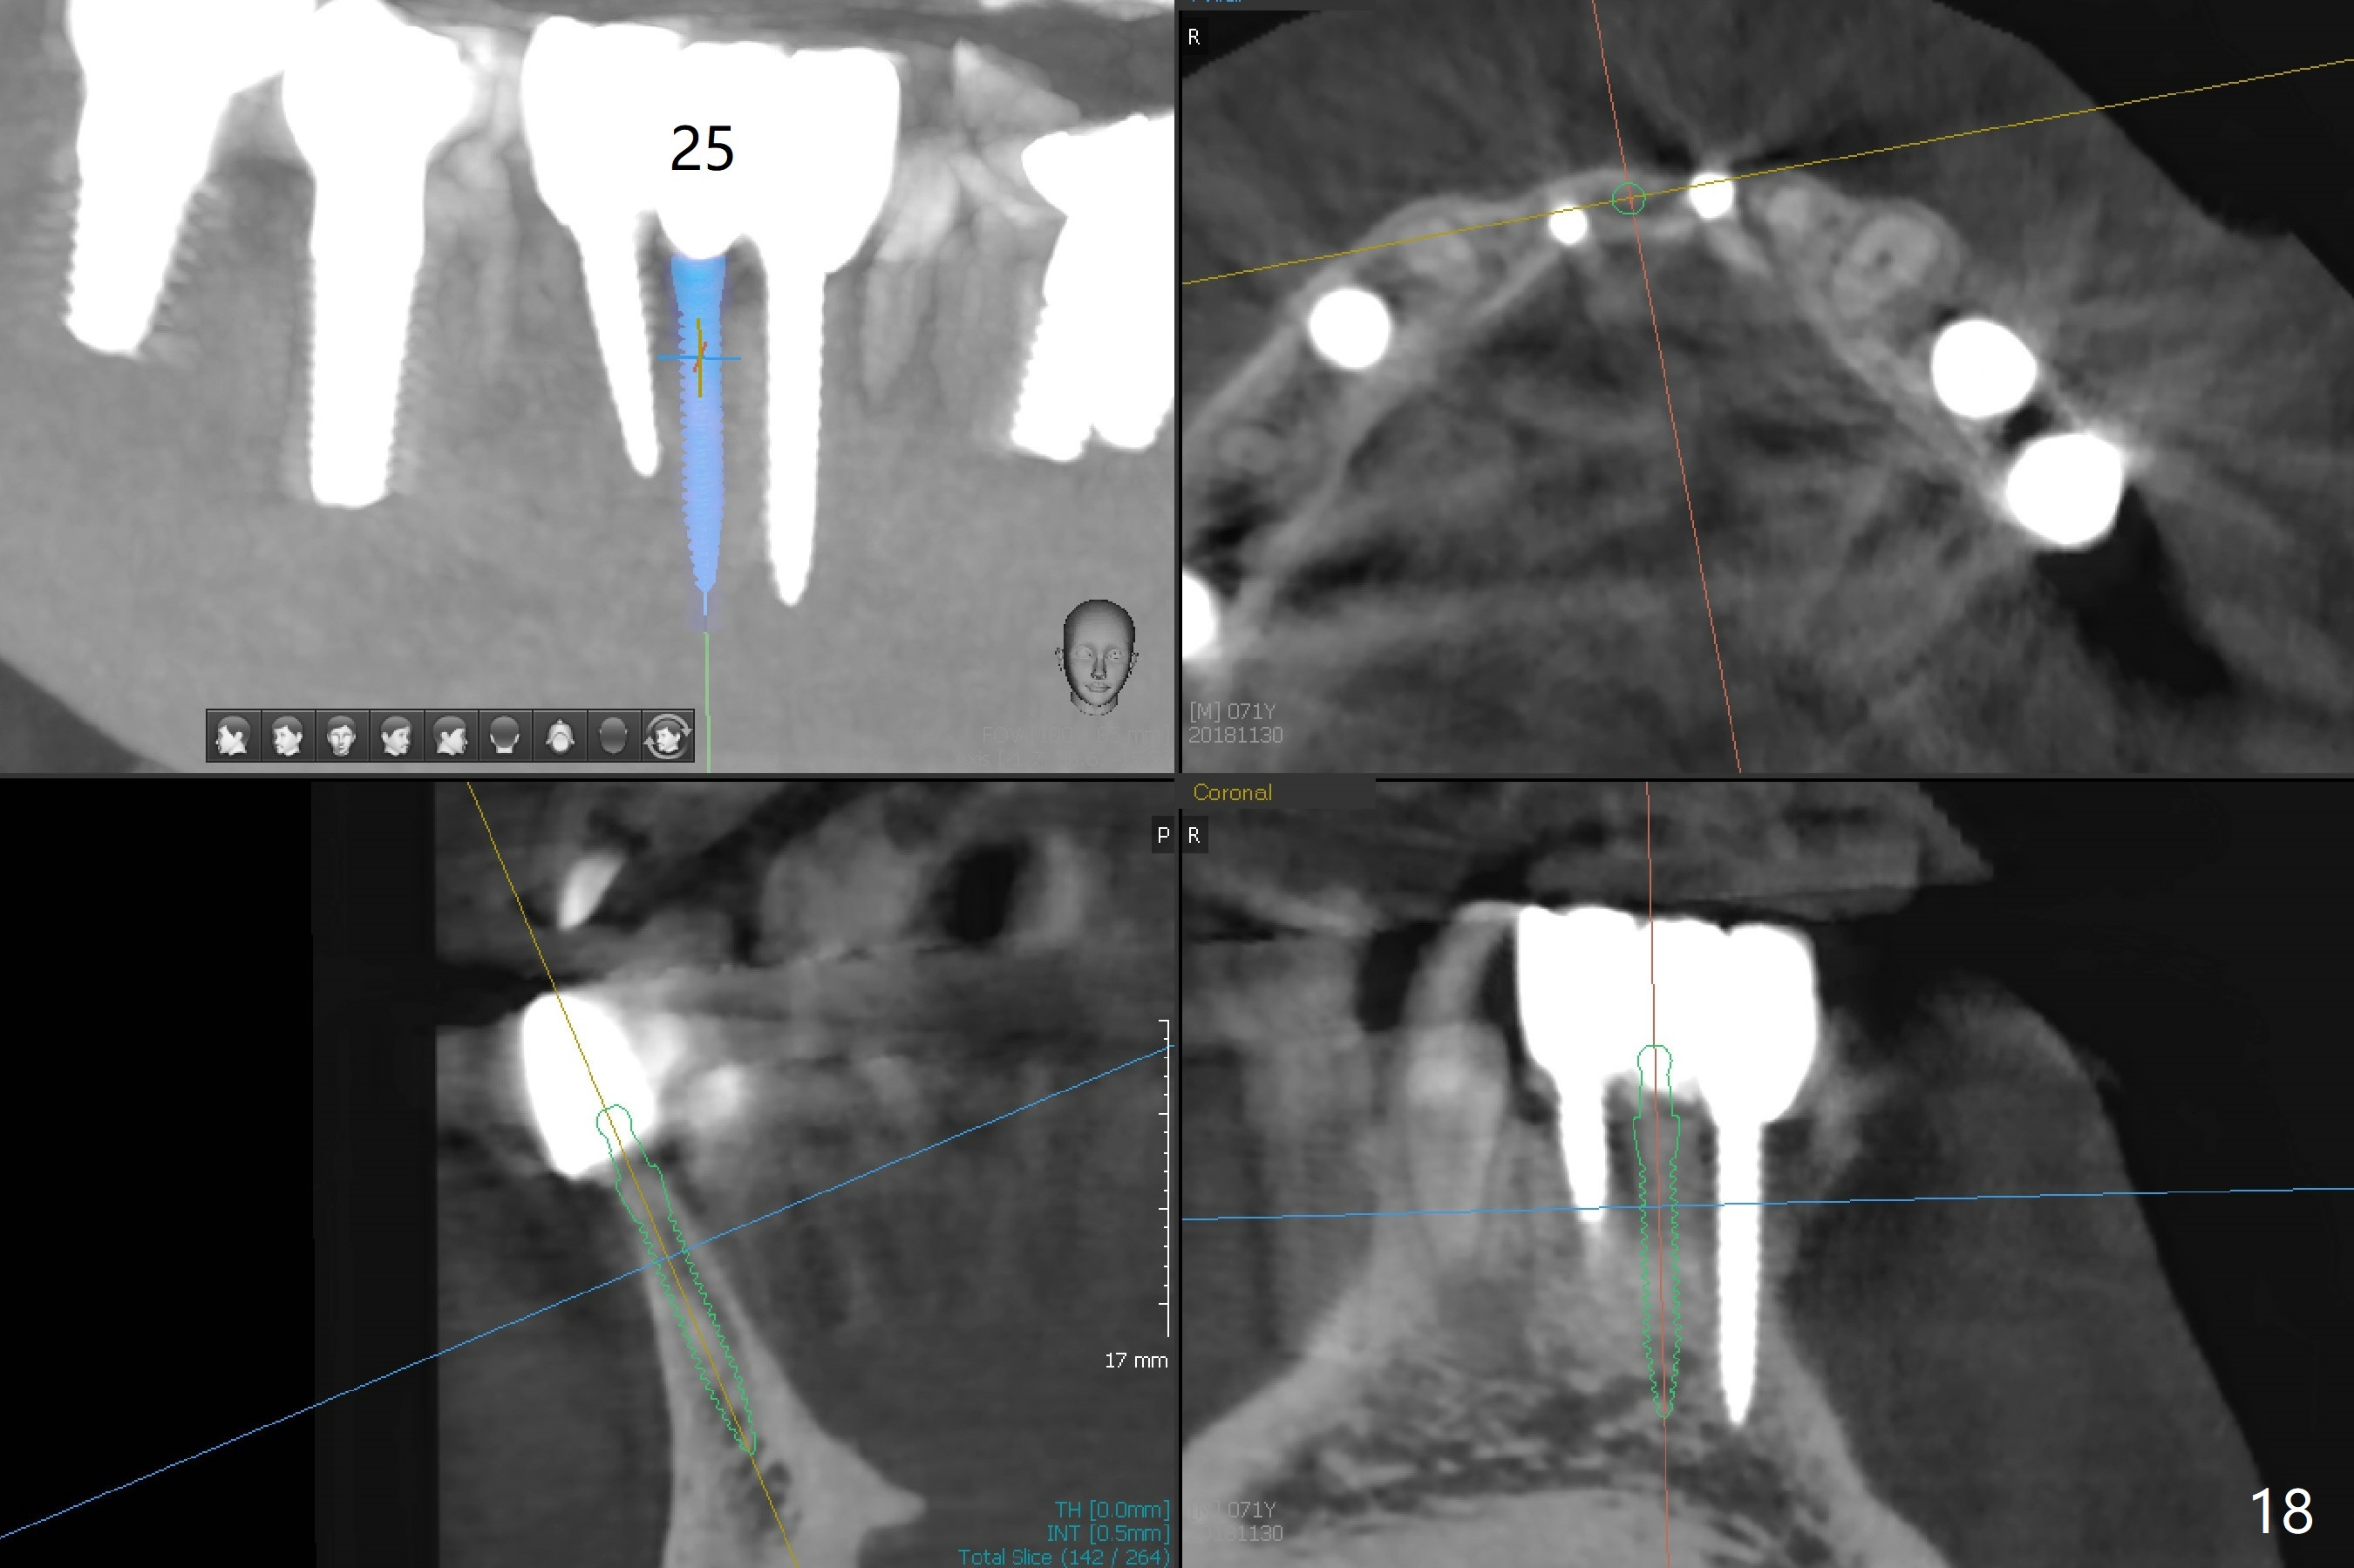

The infection persists at #26 four years 8 months post cementation (Fig.16 *). CBCT is taken. In fact the implant at #26 was placed lingual (Fig.17), while that at #24 buccal (Fig.20). The 2nd option is to remove the implant at #26 and place a 2 mm one at #25 (Fig.18,19). Fabricate a 3-unit cantilever FPD. Take 5x5 cm CT with 1.2 mm drill in place for 10 mm. Change the trajectory and position if necessary.